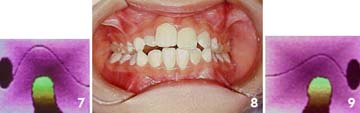

Para concluir este tema apresentaremos, como exemplo, um caso simples de mordida cruzada postural, desencadeada por respiração bucal em decorrência de uma rinite alérgica, a qual foi logo diagnosticada e convenientemente tratada. Observaremos também as prováveis implicações nas articulações temporomandibulares, estimuladas pelo uso do hiperbolóide com intuito de reprogramar o sistema estomatognático.

Com apenas seis meses de tratamento, a harmonia facial é restabelecida e o desvio postural da mandíbula deixa de influenciar a face da paciente. |